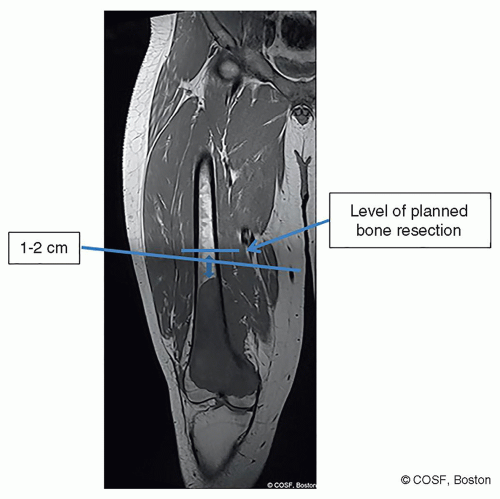

Surgical Approach (Figure 42.3)

Length of incision from below tibial tubercle to 2 to 5 cm proximal to planned bone cut (depending on thickness of soft tissue envelope) (Figure 42.4)